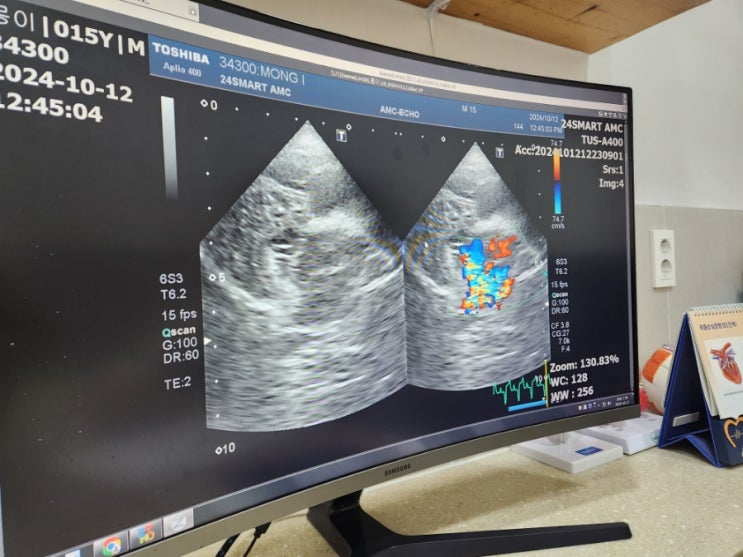

강남압구정 동물병원 강아지심장초음파 스마트동물병원 신사본원 검사 후기

강아지가 나이가 들면서 자연스럽게 내부 기관들에 질병이 생기곤 하는데요 특히 심장병은 몽이와 같은 푸...